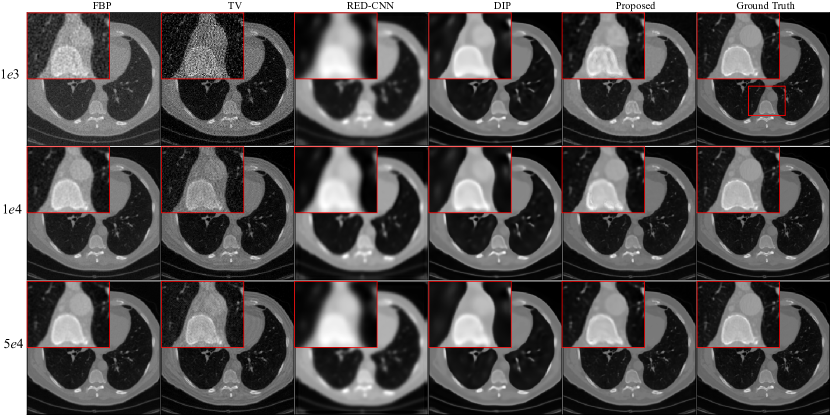

Figure 2: Reconstruction results of case AAPM-1 at different dose levels by different methods. Zoomed parts over the region of interest (ROI) marked by the red box in the ground-truth image.

Figure 3: Reconstruction results of case AAPM-2 at different dose levels by different methods. Zoomed ROI images from the ground-truth image.

Figure 4: Reconstruction results of case AAPM-3 at different dose levels by different methods. Zoomed ROI images from the ground-truth image.

AAPM challenge data: We randomly select three full-dose CT images from AAPM challenge data to evaluate effectiveness of the propose method with the X-ray source intensity Ii=[1e3,1e4,5e4]subscript𝐼𝑖1𝑒31𝑒45𝑒4I_{i}=[1e3,1e4,5e4]. From Fig. 2, Fig. 3 and Fig. 4, we can observe that the quality of the FBP reconstruction images degraded significant as the X-ray source intensity decreased, resulting in amplified noise and artifacts distributed throughout the entire image. As a post-processing method, TV achieves higher quality images by post-processing the reconstructed images through FBP. Another post-processing and supervised method RED-CNN, can effectively remove noise and artifacts, but it tends to smooth out some tiny structures. Although DIP is unsupervised and takes random noise as input, it can effectively remove noise while producing images with higher resolution than RED-CNN. Comparing the reconstructed results by different methods, we can see that the proposed method achieves the best performance in terms of noise and artifacts attenuation and preservation of tiny structures.

To better illustrate the effectiveness of the proposed method, we further demonstrate the zoomed-in results corresponding to the red box in each ground truth. As shown in Fig. 2, Fig. 3 and Fig. 4, the reconstructed results by FBP and TV are contaminated by noise and artifacts. Although RED-CNN and DIP can suppress the noise, many valuable details are smoothed out. In comparison, the proposed method achieves better reconstruction accuracy than the competitive methods. It is worth noting that although the ground-truth images are norm-dose CT images, slight noise and artifacts still remain in them. Furthermore, the reconstructed results by the proposed method outperform the ground-truth images in terms of resolution, particularly with Ii=1e4subscript𝐼𝑖1𝑒4I_{i}=1e4 and 5e45𝑒45e4.